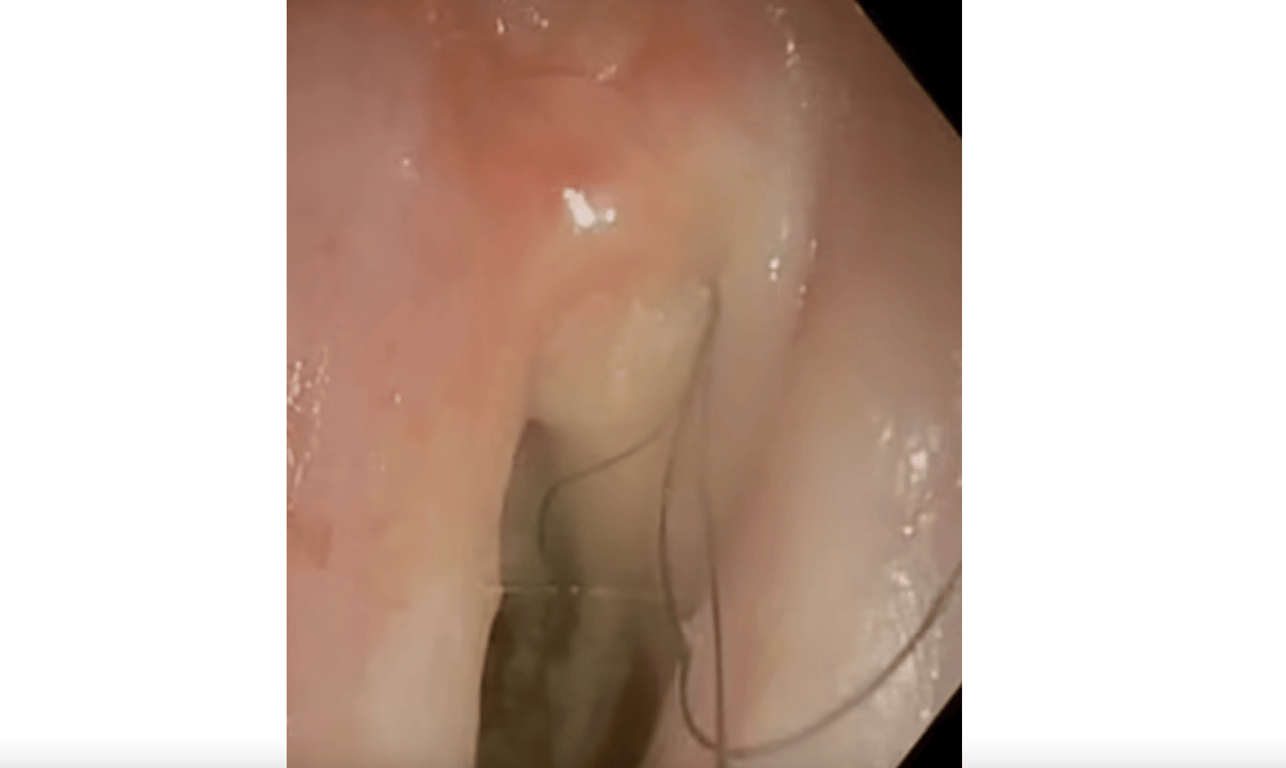

Поэтому решили дальше отправить мужчину на специальную процедуру, чтобы провести маленькую камеру по дыхательным путям. Так и удалось выявить аномалию. Из слизистой горла буквально торчали волоски!

В горле 52-летнего курильщика, выкуривавшего по пачке сигарет в день, начали расти волосы

Врачи обнаружили несколько волосков в горле. Фото: Daily Mail